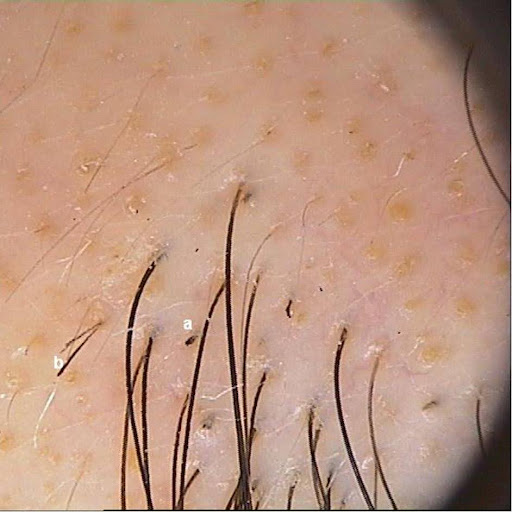

Okzipital und hochparietal rechts finden sich insgesamt drei zwischen 3 und maximal 7cm durchmessende ovaläre scharf begrenzte Kahlstellen. Die Kopfhaut ist dabei vollkommen reizfrei und das verbliebene Kopfhaar kräftig und gesund. Dermatoskopisch sind auch intraläsional noch erhaltene Haarfollikel erkennbar, daneben mehrere sogenannte „Ausrufezeichenhaare“ (Abb. 1).

Abb. 1: Scharf begrenzte und oval umschriebene haarlose Areale auf reizfreier Kopfhaut (a-d). In der Dermatoskopie finden sich erhaltene Haarfollikel sowie sichtbare kurze ausgefranste Haarstümpfe („Ausrufezeichenhaare“) (e,f).

Schon blickdiagnostisch sind die fast kreisrunden scharf abgegrenzten haarlosen Läsionen auf reizfreier Haut als Alopecia areata zu erkennen. Der dermatoskopische Aspekt sichert die Diagnose. Sichtbar sind einzelne und gruppierte pathognomonische „Ausrufezeichenhaare“ in den Randgebieten als auch inmitten der aktiven und progredienten Alopezieherde. Diese auch „Kadaverhaare“ oder „Kommahaare“ genannten 0,2-0,6 cm kurzen Haare haben Trichorrhexis-artig aufgesplitterte freie Enden, die sich zum Follikel hin verjüngen. Sie sind pathognomonisch für die Alopecia areata.